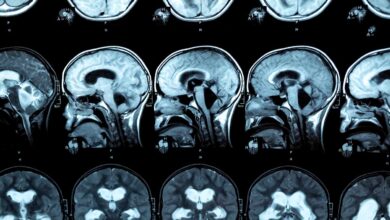

مغز و اعصاب